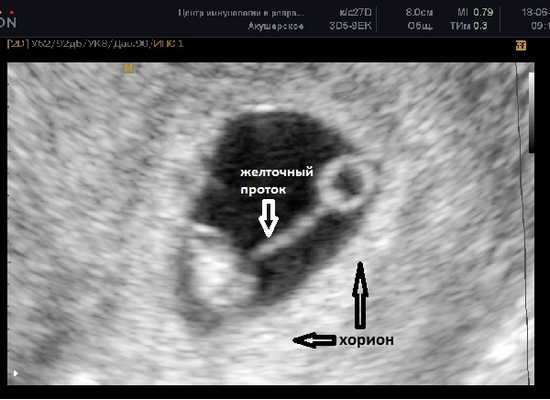

Расстояние между эмбрионом и желточным мешком постепенно увеличивается и становится хорошо различим желточный проток (ductus vitellinus), соединяющий между собой желточный мешок и кишечник эмбриона. Так же, как и желточный мешок, проток на более поздних сроках запустевает и рассасывается, но если это не происходит по каким-то причинам, то у человека формируется слепое выпячивание стенки подвздошной кишки - дивертикул Меккеля.

До этого срока хорион имеет кольцевидную форму, окружает плодное яйцо со всех сторон и пока ещё нельзя сказать к какой стенке матки прикрепился эмбрион.

В случае монохориальной двойни ещё не видно амниотических оболочек и при наличии двух желточных мешков всё ещё нельзя сказать является ли данная беременность моно или диамниотической. Если плодное яйцо содержит два желточных мешка и два плода с наличием сердечной активности, в последующем количество амниотических полостей может быть больше, чем количество плацент (монохориальная диамниотическая) или одинаковым (монохориальная моноамниотическая). В этом случае точно определить амниональность возможно после 8 недель, когда амниотические оболочки начинают четко визуализироваться.

ЧСС эмбриона 130-160 ударов в минуту.

СВД плодного яйца 24-30 мм, КТР эмбриона 9-15 мм.